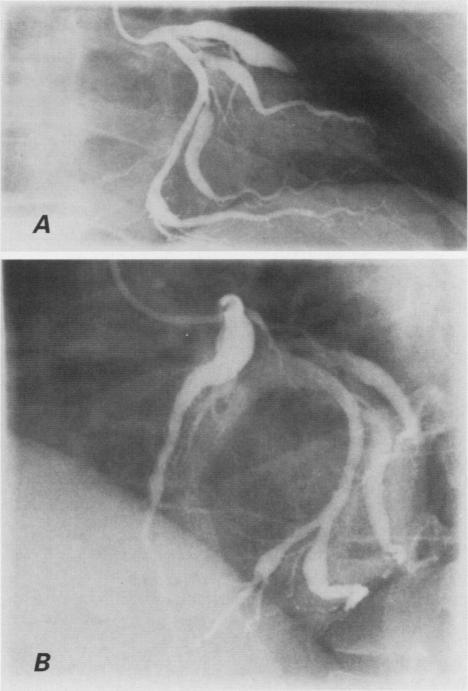

埃及冠心病患者的冠状动脉扩张

Coronary artery ectasia in Egyptian patients with coronary artery disease.

We conducted a retrospective study of 45 Egyptian patients with coronary artery ectasia who underwent coronary bypass grafting at our institution between 1980 and 1995. We examined the anatomic distribution and type of coronary ectasia and its association with coronary risk factors in these patients, and evaluated the severity of their coronary artery disease. We compared these findings with those from a group of 230 Egyptian patients who did not have coronary ectasia. These patients also underwent coronary artery bypass grafting between 1980 and 1995 at our institution. Obesity was present in 60% of the patients who had coronary artery ectasia, compared with 42% of patients who did not have ectasia (P < 0.01). Coronary artery ectasia was not related to any coronary risk factors other than obesity. However, patients who had ectasia did have a higher rate of triple-vessel coronary artery disease than did patients without ectasia (82% vs 67%, P < 0.05). Of the coronary vessels affected by ectasia, 43% were left anterior descending arteries. Diffuse disease was noted in 84% of all ectatic segments. We conclude that in this patient population, 2 conditions had a positive correlation with coronary ectasia: obesity and the severity of coronary artery disease.

我们对1980年至1995年间在我院接受冠状动脉旁路移植术的45例埃及冠状动脉扩张患者进行了一项回顾性研究。我们检查了这些患者冠状动脉扩张的解剖分布、类型及其与冠状动脉危险因素的关联,并评估了他们冠状动脉疾病的严重程度。我们将这些结果与一组230例无冠状动脉扩张的埃及患者的结果进行了比较。这些患者也于1980年至1995年间在我院接受了冠状动脉旁路移植术。60%有冠状动脉扩张的患者存在肥胖,而无扩张的患者中这一比例为42%(P<0.01)。除肥胖外,冠状动脉扩张与任何冠状动脉危险因素均无关联。然而,有扩张的患者三支血管冠状动脉疾病的发生率高于无扩张的患者(82%对67%,P<0.05)。在受扩张影响的冠状动脉血管中,43%为左前降支动脉。在所有扩张节段中,84%发现有弥漫性病变。我们得出结论,在这一患者群体中,有两种情况与冠状动脉扩张呈正相关:肥胖和冠状动脉疾病的严重程度。